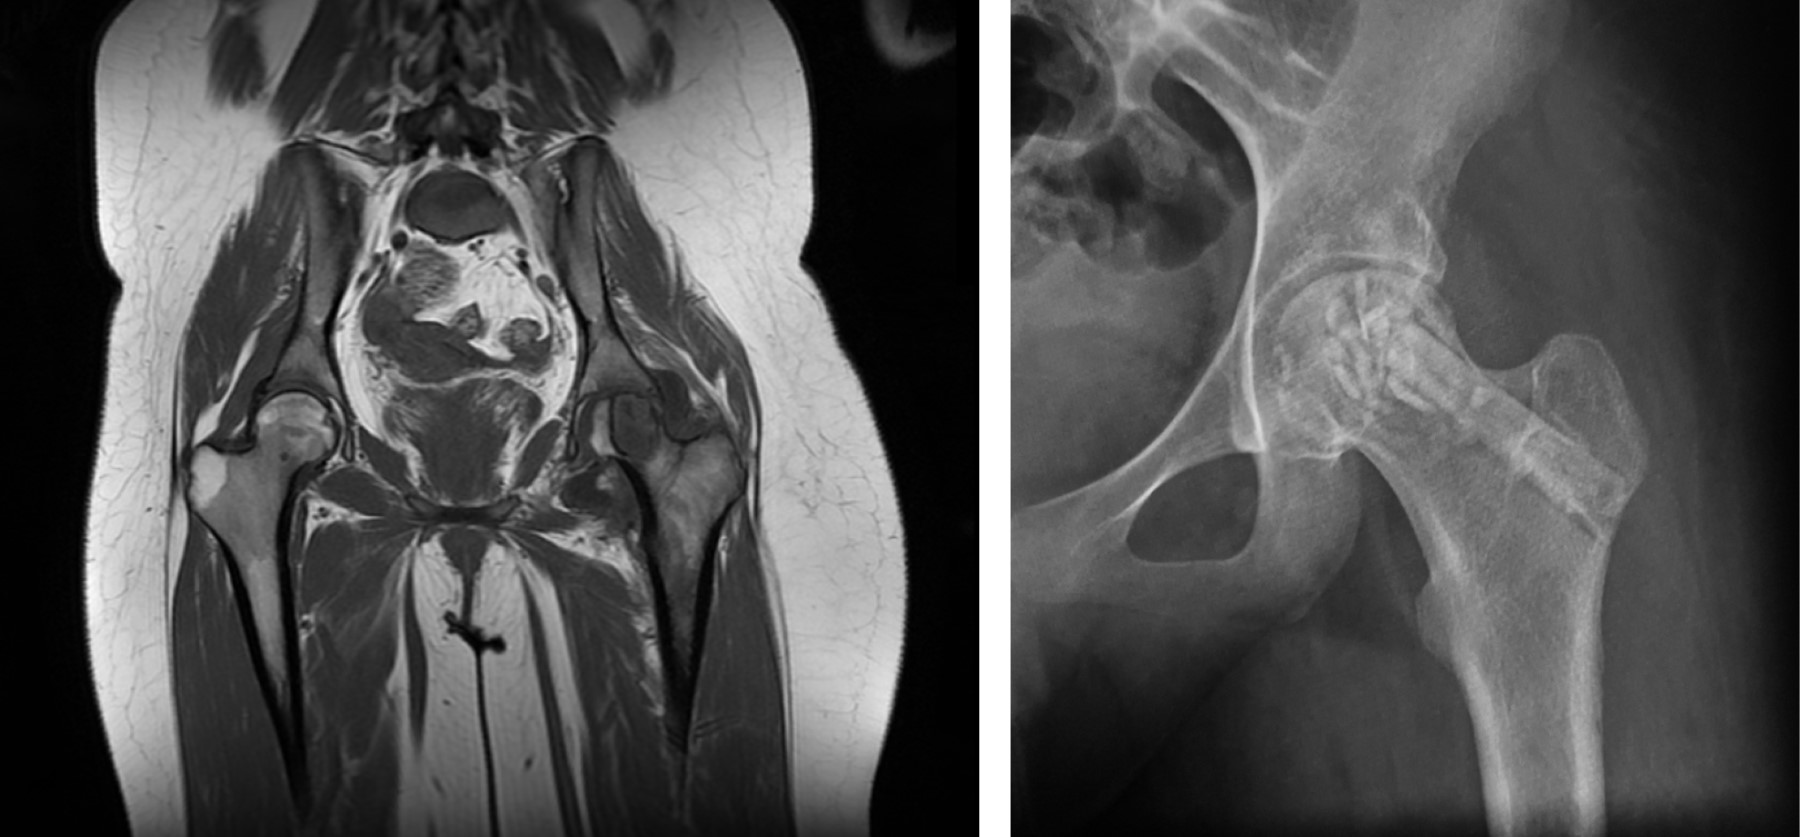

Caso 1. Paciente masculino de 18 años que, posterior a trauma deportivo indirecto, inició con coxalgia izquierda. Radiológicamente se identificó una lesión osteolítica que involucra la región cérvico-trocantérica mayor en el fémur proximal. Se complementó su estudio desde el punto de vista imagenológico con tomografía computarizada y resonancia magnética, las cuales confirmaron integridad cortical y niveles hídricos en su interior. La biopsia llegó al diagnóstico de quiste óseo aneurismático. Esta lesión es definida como una neoplasia ósea benigna que contiene espacios quísticos multiloculados llenos de sangre.9 El paciente fue llevado a un tratamiento intralesional en cuyo defecto generado se adiciona un segmento diafisario de aloinjerto liofilizado de peroné, además de chips de aloinjerto cortico-esponjoso. La evolución postoperatoria resultó satisfactoria y la prohibición al soporte de carga fue de tres meses, con la indicación de no restringir la movilidad. La consolidación de la zona se logró a los cuatro meses del evento quirúrgico, así como la autorización para el soporte total de carga (Figura 1).

Caso 3. Paciente femenino de 17 años quien, posterior a embarazo, inició con coxalgia izquierda. En las radiografías convencionales se observó una imagen osteolítica circular en la epífisis proximal del fémur cuya placa fisaria o de crecimiento ya se encuentra cerrada. La superficie articular en la cabeza femoral permanece íntegra, pero en riesgo inminente de colapsarse. Los cortes de tomografía y resonancia magnética confirmaron integridad ósea y articular. La biopsia indicó que se trataba de un condroblastoma, razón por la cual se realizó resección intralesional con aporte de aloinjerto cortico-esponjoso subcondralmente e inmediato a éste, aloinjerto diafisario de peroné liofilizado, reforzando tanto la lesión como el trayecto cérvico-trocantérico para llegar a ella. El condroblastoma es definido como un tumor óseo benigno que tiene predilección epifisaria o apofisaria, compuesto de células condroblásticas e islas de matriz condroide eosinofílica.11 Por riesgo de colapso articular y de fractura transcervical, se restringió el soporte de carga por tres meses y éste se permitió con incremento progresivo hasta hacerse total durante los siguientes dos meses. Por tratarse de una lesión localizada subcondralmente en una articulación que no permite mínimas incongruencias, continuaremos vigilando por si en algún momento la paciente desarrolla colapso articular con la consecuente artrosis (Figura 3).

Figura 1

Figura 3